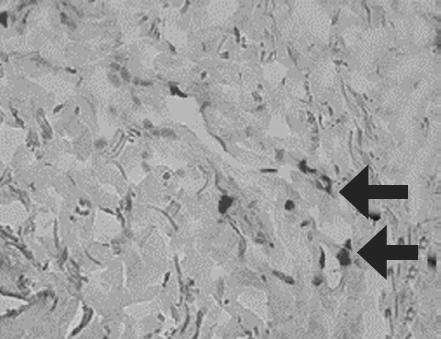

Histological examination of biopsy samples taken from the area of ATMSC transplantation for all the patients revealed the presence of pronounced vascularization with the perifocal proliferation of fibroblasts in both the superficial and deep layers of the dermis (Fig. 6, 7). An immunohistochemical study revealed that the use of ATMSCs resulted in a 5.6-fold increase in the expression of proliferation markers of epithelial and connective tissue cell lines in the injection area (p < 0.01) (proliferation 2.1–2.2), and that apoptotic activity was completely suppressed (Fig. 8, 9). Laser Doppler flowmetry assessment of the microcirculation in the area of stem cell injection on day 7 after early necrectomy, skin grafting, and the administration of MMSCTM showed double the average level of perfusion and mean square deviation of the amplitude of blood flow oscillations than for areas where MMSCTM was not used (p < 0.05) (Table 6).

Fig. 8. Patient D., 34 years old. Significant expression of the proliferation marker of Ki 67 cells of an autologous cutaneous graft on the 5th day after the AMSC injection. Zoom ×600

Рис. 8. Пациент Г., 34 года. Выраженная экспрессия маркера пролиферации Ki-67 клетками аутологичного кожного трансплантата на 5-е сутки после введения мезенхимальных стволовых клеток жировой ткани. Увеличение ×600